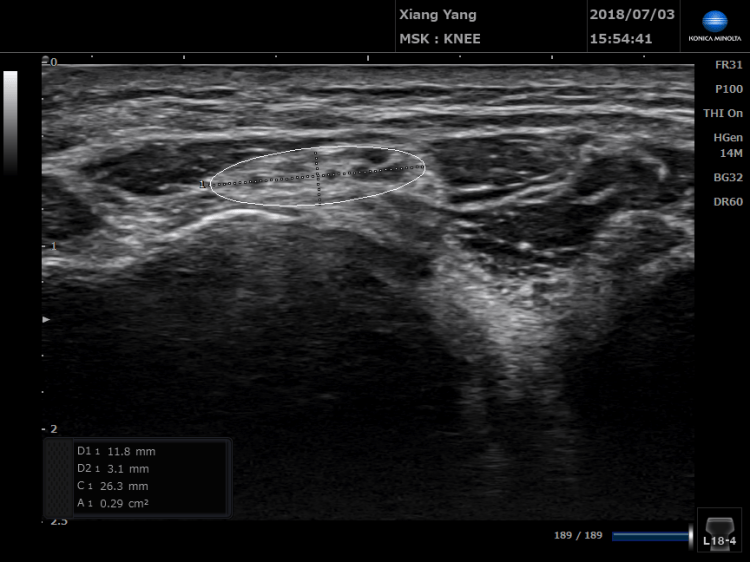

以往診斷肘隧道症候群可依靠神經肌電學檢查,透過扎針和電極去量測神經傳導的速度。如果在通過肘隧道的地方神經傳導速度變慢,就可以診斷。不過因為超音波技術逐漸發展,表淺性的神經構造可以透過超音波檢測看到,也因此逐漸發展出超音波在神經病變的診斷。肘隧道如果神經截面積超過一定數值,也就是神經比較腫脹,配合理學檢查,已經可以達到與神經肌電學檢查的診斷率相當的結果。

透過超音波檢查到的神經病變,可以透過"神經解套"治療,透過低濃度葡萄糖的注射解除這邊神經的壓迫。